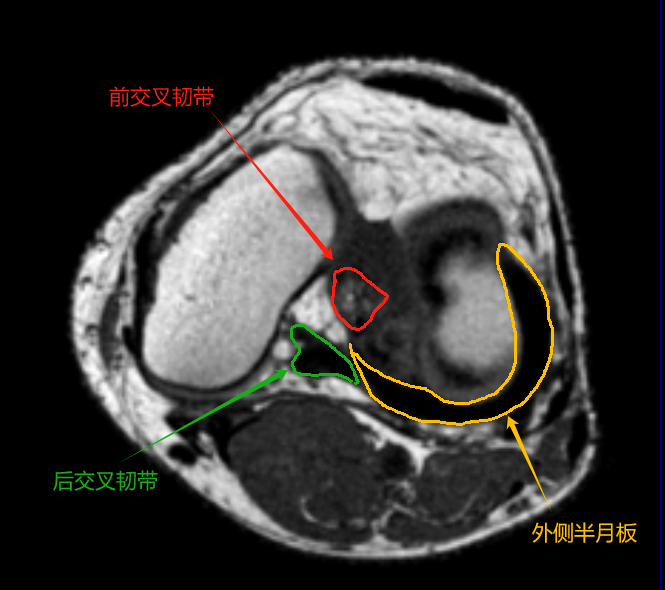

2. 半月板

• 内侧半月板:C形,边缘与关节囊相连;

• 外侧半月板:O形,后角与腘肌腱相邻。

1. 韧带与肌腱

• 前交叉韧带(ACL):外侧髁间嵴至股骨外侧髁内侧面,轴位呈束状低信号。

• 后交叉韧带(PCL):胫骨后方至股骨内侧髁,轴位为卵圆形低信号结构。